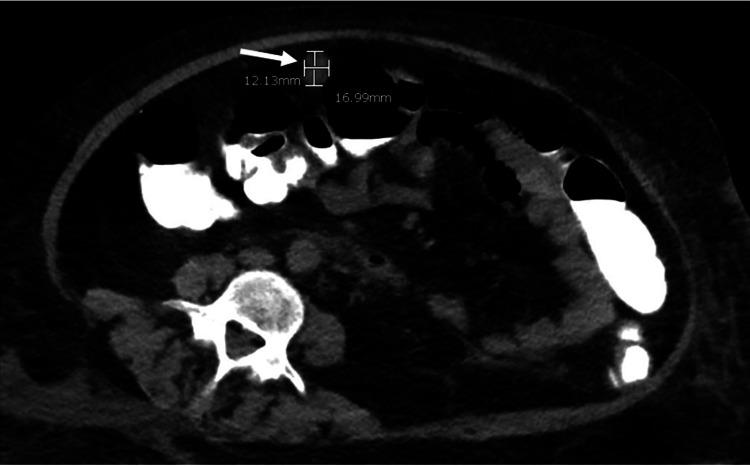

库欣综合征(CS)是一种免疫功能低下状态,其特征为因皮质醇增多症导致细胞免疫和适应性免疫受损。免疫系统的这种失衡会导致机会性感染的高风险,而这些感染可能会致命。对于此类患者,通过早期诊断和有效控制潜在的皮质醇增多症可降低死亡率。在本病例报告中,我们描述了如何通过低剂量持续输注依托咪酯迅速降低皮质醇水平,这对一名患有库欣综合征的29岁女性有效治疗机会性感染——播散性诺卡菌病起到了关键作用。我们还讨论了使用抗生素治疗,包括用亚胺培南和磺胺甲恶唑/甲氧苄啶(SMX/TMP)进行经验性治疗,以及根据药敏试验用阿米卡星、SMX/TMP和强力霉素进行确定性治疗,如何有助于预防不良后果。通过这个病例,我们旨在强调,库欣综合征患者胸部计算机断层扫描(CT)上的浸润或空洞性病变应引起对诺卡菌病的关注,并应立即开始用抗生素进行治疗。同样,播散性诺卡菌病应始终引起对可能的免疫缺陷状态如库欣综合征的关注。我们的病例独特之处在于详细阐述了在患有内源性库欣综合征和广泛侵袭性机会性感染的患者中使用依托咪酯急性降低皮质醇水平的重要性。在本病例中,依托咪酯的药理学方面已发表在《药学实践杂志》上,并在本文中适当引用。

https://cdn.ncbi.nlm.nih.gov/pmc/blobs/3a1b/8729312/6be9fc1620b3/cureus-0013-00000020214-i03.jpg

https://cdn.ncbi.nlm.nih.gov/pmc/blobs/3a1b/8729312/9a38a14fcc1c/cureus-0013-00000020214-i01.jpg

https://cdn.ncbi.nlm.nih.gov/pmc/blobs/3a1b/8729312/ea99b29df897/cureus-0013-00000020214-i02.jpg